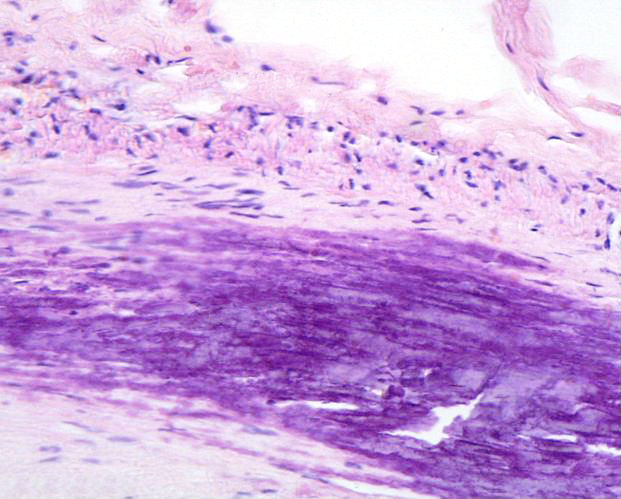

back atherosclerotic plaque

Source: Calcificatio atherosclerotica.jpg